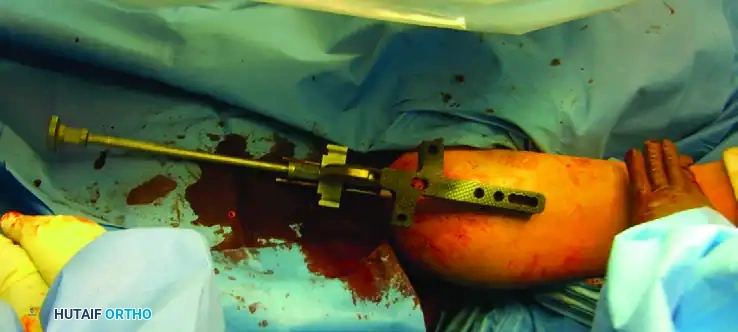

Antegrade Intramedullary Nailing: Techniques and Controversies

The antegrade approach is the most frequently utilized technique for humeral nailing in adults. However, the exact placement of the entry portal remains a subject of intense academic debate.

- Anterolateral Portal: Modern techniques advocate for an anterolateral starting point. This portal aligns perfectly with the linear axis of the humeral medullary canal. Crucially, the incision through the rotator cuff is made longitudinally, in line with the tendon fibers, facilitating anatomic repair and theoretically reducing postoperative shoulder pain.

Preferred Technique: Rigid Antegrade Locked Nailing

Step-by-Step Execution:

- Preparation: Position the patient in the beach-chair or supine position. Ensure the C-arm can visualize the humerus from the humeral head to the elbow joint.

- Incision and Entry: Utilize an anterolateral incision. Split the deltoid and incise the rotator cuff in line with its fibers. Establish the entry portal just medial to the greater tuberosity, directly in line with the medullary canal.

- Proximal Locking: Utilize the outrigger targeting device to insert the proximal locking screws. Ensure the axillary nerve is protected during this step by using soft tissue sleeves.